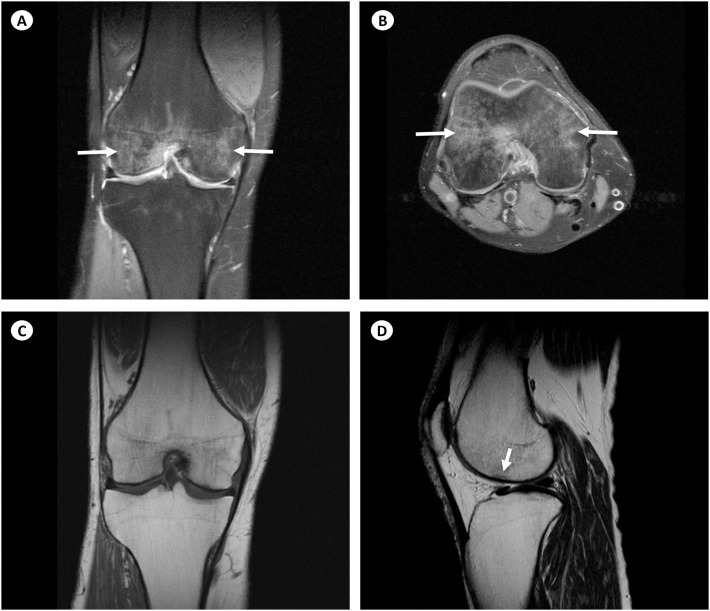

Regional Migratory Osteoporosis.